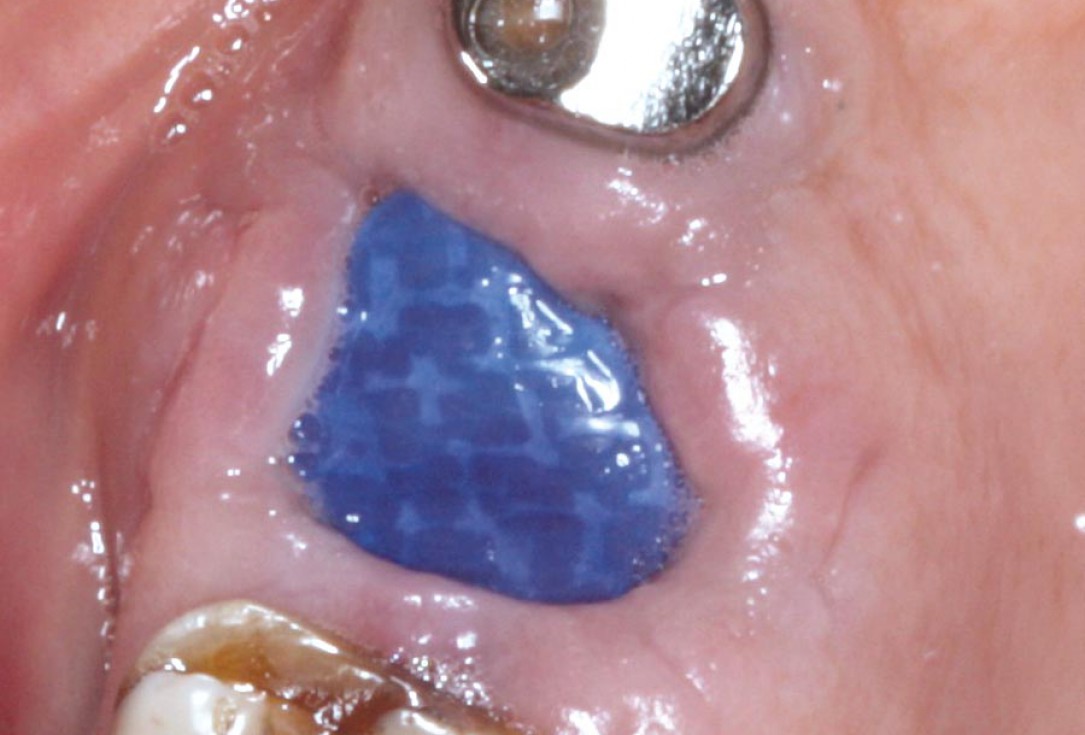

06/07 - Situation 2 weeks post-operative.Socket preservation with permamem® - Dr. M. Turco